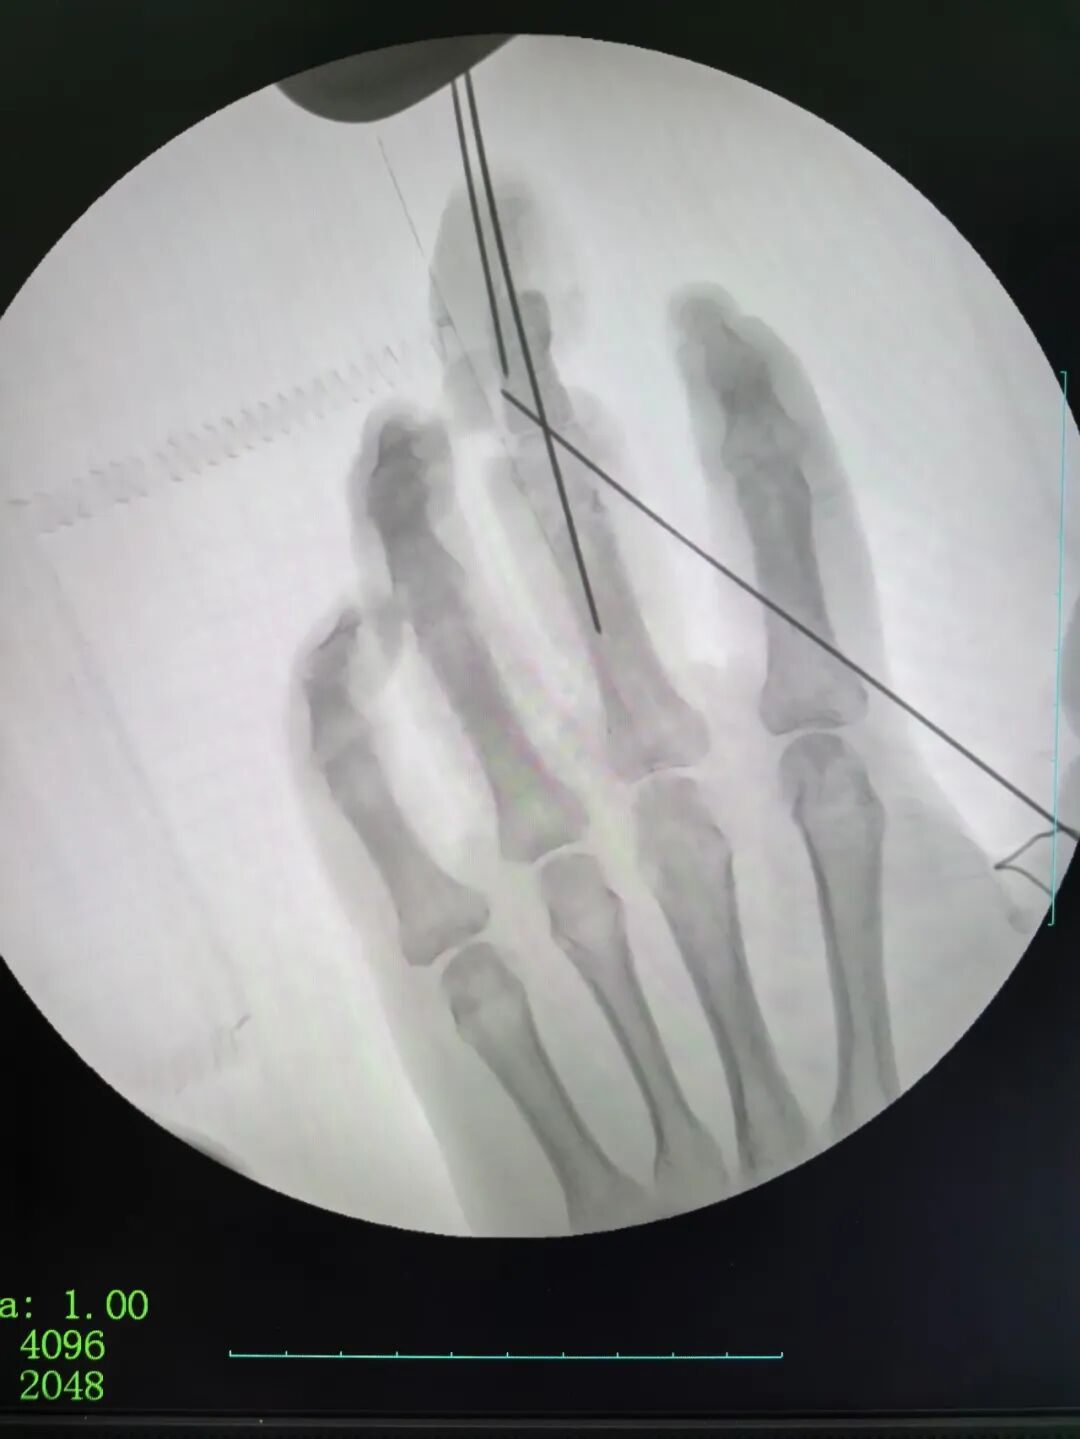

2026年1月1日,手足显微修复重建专家刘金海及其团队已坚守在手术台前,成功为一位远道而来的手指缺损患者完成显微修复重建手术,以医者的责任与担当开启新岁。刘金海在开年寄语中如是写道:

2026年的第一天,新年的钟声还在耳畔回响,我和我的团队却已在手术室为一位远道而来的手指缺损患者完成了显微修复重建手术。以一台手术开启新岁,于我而言,既是医者的日常,更是对“健康所系,性命相托”誓言的践行。

擅长手指美学再造及超级显微外科技术,首创“指尖美学再造”技术,累计完成1000余例手术,兼顾功能与外观。

2016年带领团队完成世界第30例十指离断再植手术,全部成活,获中国工程院院士顾玉东高度评价。